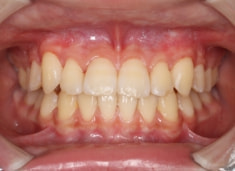

治療前

治療開始時

FX(フェイシャルアキシス)は85度なので東洋人の平均値に近く、下顎が前方に過剰成長するリスクは強くはありません。

しかしやはり上顎は劣成長で、下顎が優位な状態ではあります。

上下顎のギャップはありますが、顔面自体の幅径は良好な値を示していますので、スペース不足は拡大することによって解決できポテンシャルはあると考えられます。

左右の非対称もさほど強くありません。